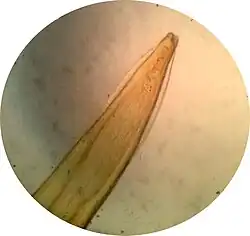

L'adulte mesure de 10 à 18 cm de longueur pour 1 à 2 mm de diamètre et présente une couleur blanc nacré. Il est souvent observé partiellement enroulé sur lui-même. L'extrémité antérieure portes deux ailes cervicales latérales dites en fer de lance. La bouche est entourée de trois lèvres développées.